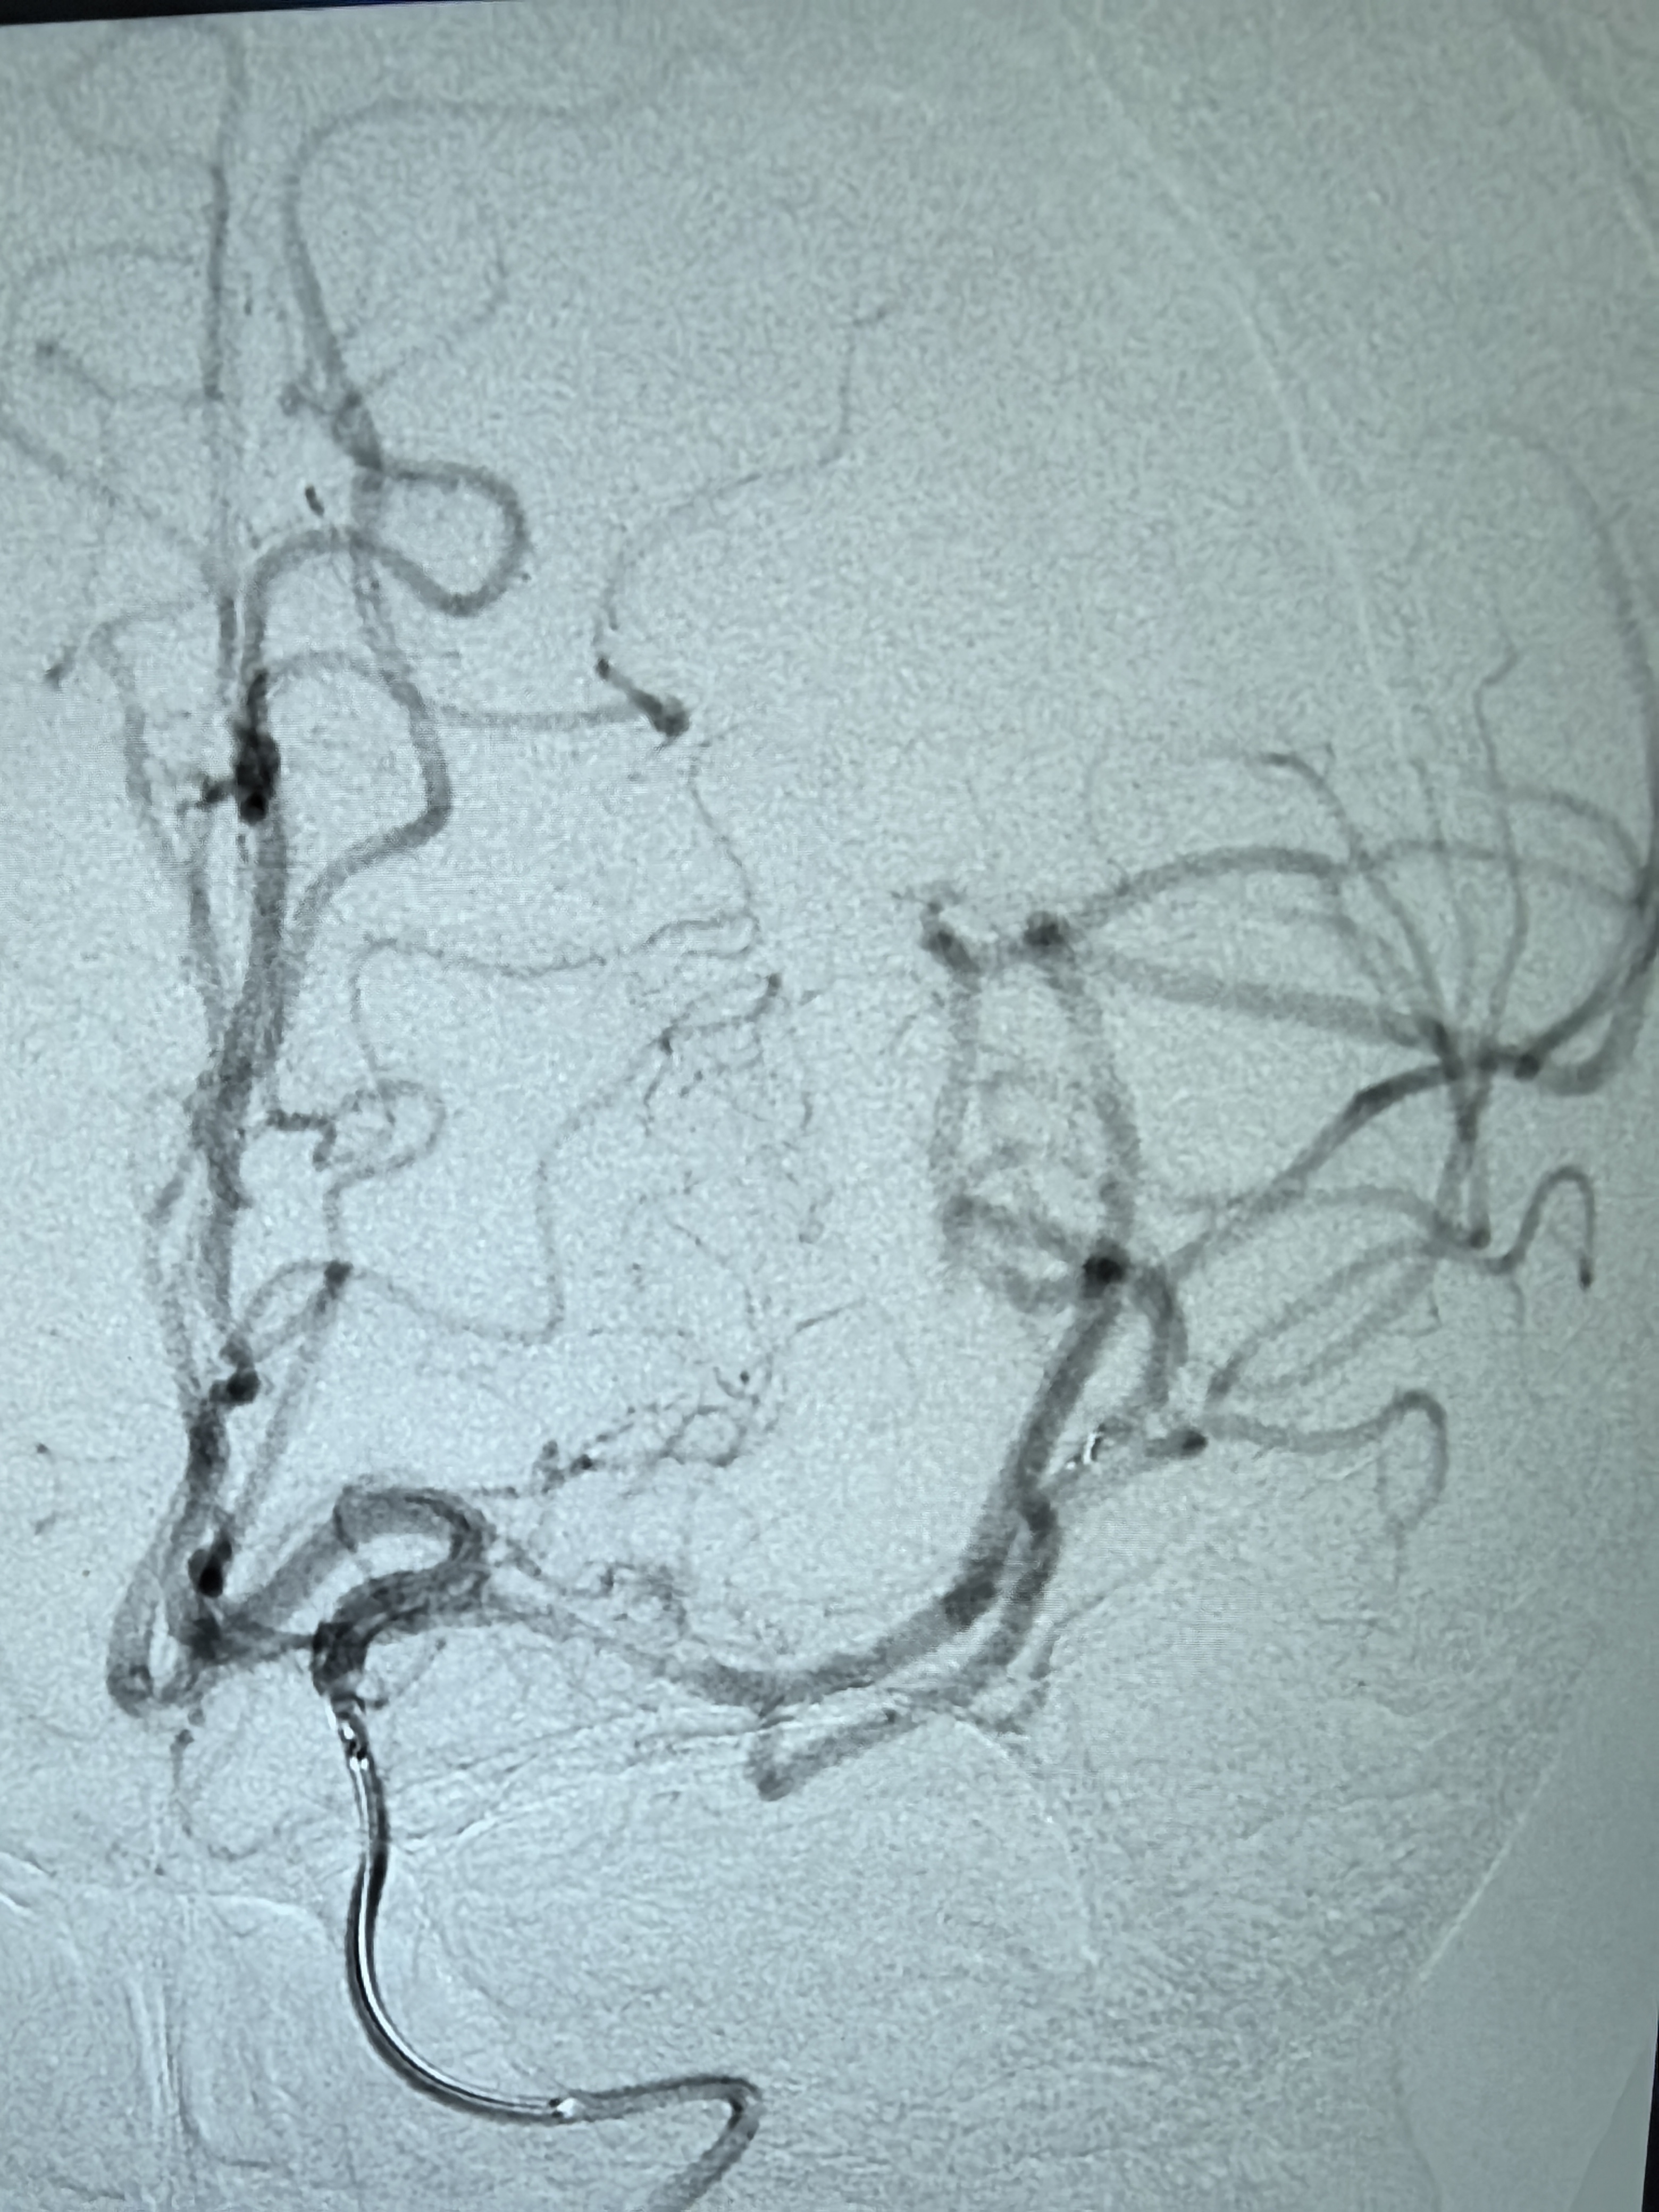

1、本例患者老年女性,系骨科术后次日醒后卒中,经核磁评估提示左侧大脑中动脉闭塞,系责任血管,患者心电图示房颤,考虑心源性栓塞可能性大。

2、本例患者SWIM技术取栓一次后血管再通,颅内血流通畅。